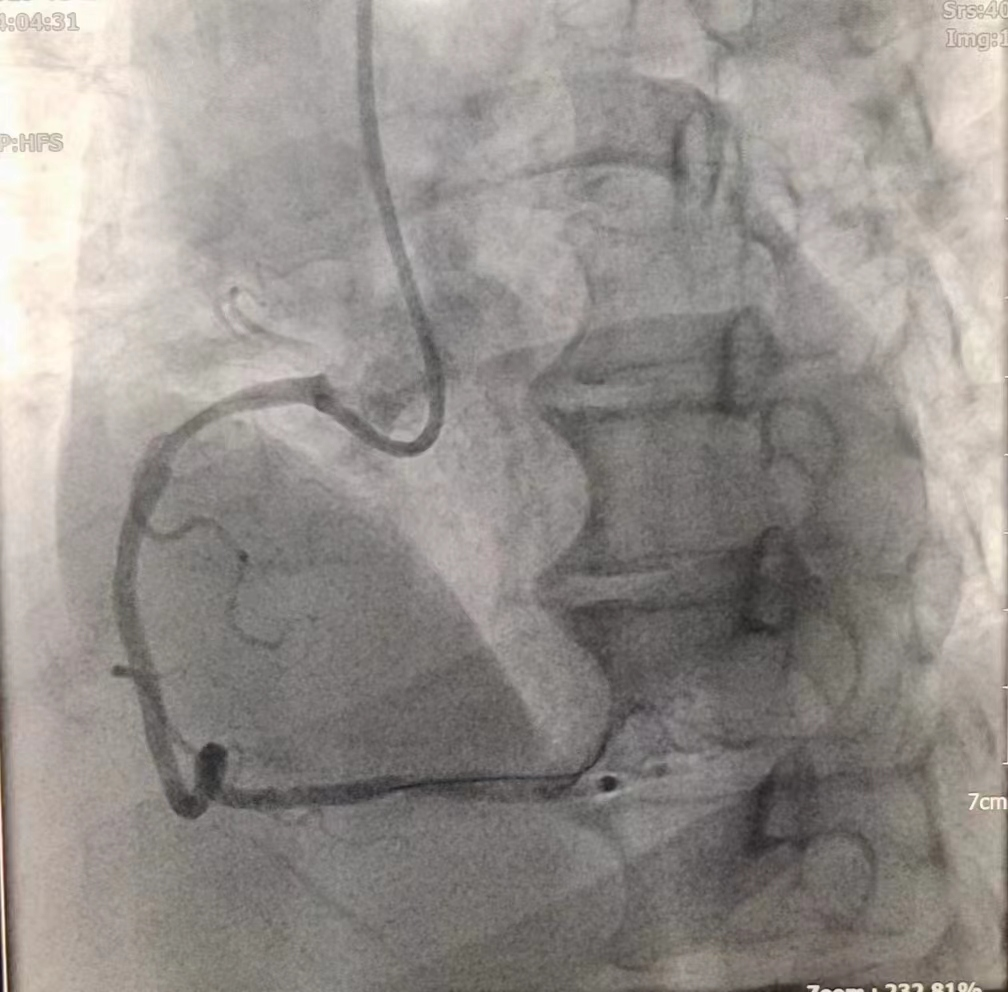

女性患者,49歲,突發暈厥急診我院,經診斷為:冠狀動脈粥樣硬化性心臟病、2型糖尿病。導入造影導管行冠狀動脈造影示:冠狀動脈分布呈左冠優勢型,LM未見明顯狹窄,血流TIMI3級;LAD全程多發斑塊,中段狹窄約60%,遠端狹窄約50%,D1未見明顯狹窄,血流TIMI3級;LCX未見明顯狹窄,血流TIMI3級,RCA近端狹窄約50%,中段發出圓錐支后完全閉塞,血流TIMI0級,急診開通血管并充分擴張,殘余狹窄仍然嚴重。在與患者及家屬溝通時,其了解得知臨床有一種新型的可吸收支架,植入體內后支架能完全被降解和吸收,希望能用這種新型的支架進行手術治療。由于生物可吸收支架有著嚴格的適應癥,因此經過嚴格篩選評估,最終對患者進行了Xinsorb生物可吸收支架置入術。支架植入術前經過充分預擴張,按照規范的可吸收支架操作流程,快速送入可吸收支架到病變部位,精準定位后14個大氣壓釋放,生物可吸收支架后擴球囊擴張。充分球囊后擴張,以保證支架貼壁良好,血流速度正常,造影完美,手術順利結束。

(圖為右冠病變術前影像)